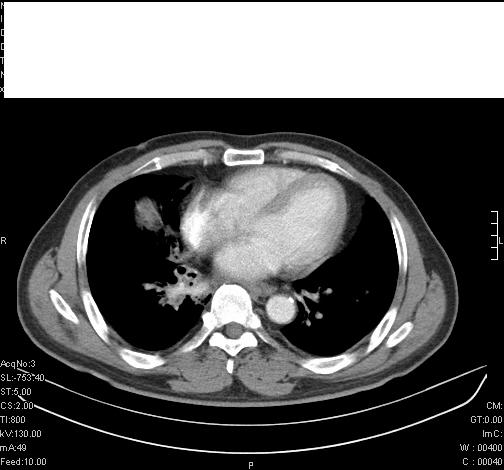

标题: CT6685:右肺阻塞性炎症,增强CT。

前几天,发了患者的平扫片,患者抗炎一周后增强扫描。右中叶病灶吸收明显,但下叶病灶未见明显吸收。右肺门可见结节影,看来凶多吉少

右肺下叶支气管管腔狭窄,管壁增厚,右下肺见斑片状高密度影,考虑右侧肺门中心肺癌伴阻塞性肺炎

右肺下叶散在的斑片状致密影,下叶支气管变窄。考虑:右肺慢性炎症。

右肺下叶支气管壁不规则增厚,右肺下叶有斑片状影分布。考虑右肺中央型肺癌伴右肺下叶阻塞性改变。建议支纤镜检查。平扫比增强较好显示了病变情况。

右主支气管狭窄,管壁增厚。考虑右中心性肺ca伴阻塞性肺炎。

既然抗炎治疗有效,可继续治疗;右肺下叶支气管管腔狭窄,管壁增厚,右下肺见斑片状高密度影,右侧主支气管后见结节影(淋巴结?),肺癌不能排出。